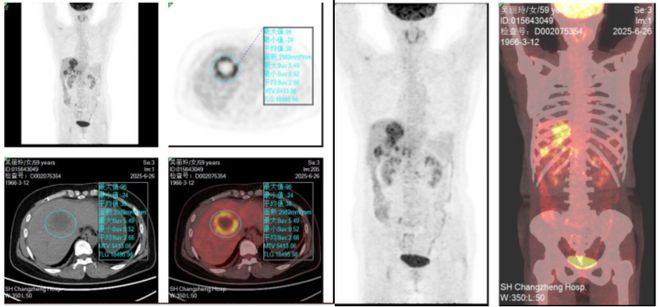

PET-CT提示:1、肝内多发病变伴腹膜后及盆腔多发肿大淋巴结,考虑恶性转移。 2、双肺多发小结节,建议胸部CT随访。3、可见双肺纤维灶、冠脉钙化斑块及子宫肌瘤等伴发病变。